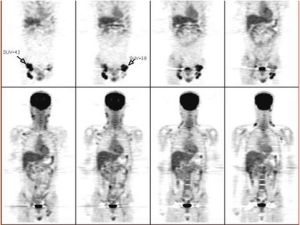

惡性淋巴瘤的病理診斷一經確定,為了解病灶的擴散情況,需要做全身檢查。體表的淋巴結經觸診可測定,腹膜後淋巴結可通過CT和腹部超音波診斷加以明確。CT和B超檢查也可明確肝、脾等腹腔內臟器的異常。

套用放射性同位素Y射線掃描檢查,可探知體內潛在的腫大的淋巴結。淋巴瘤細胞多可隨血流周轉全身,所以骨髓穿刺檢查,明確其有否骨髓內轉移也實屬必要。